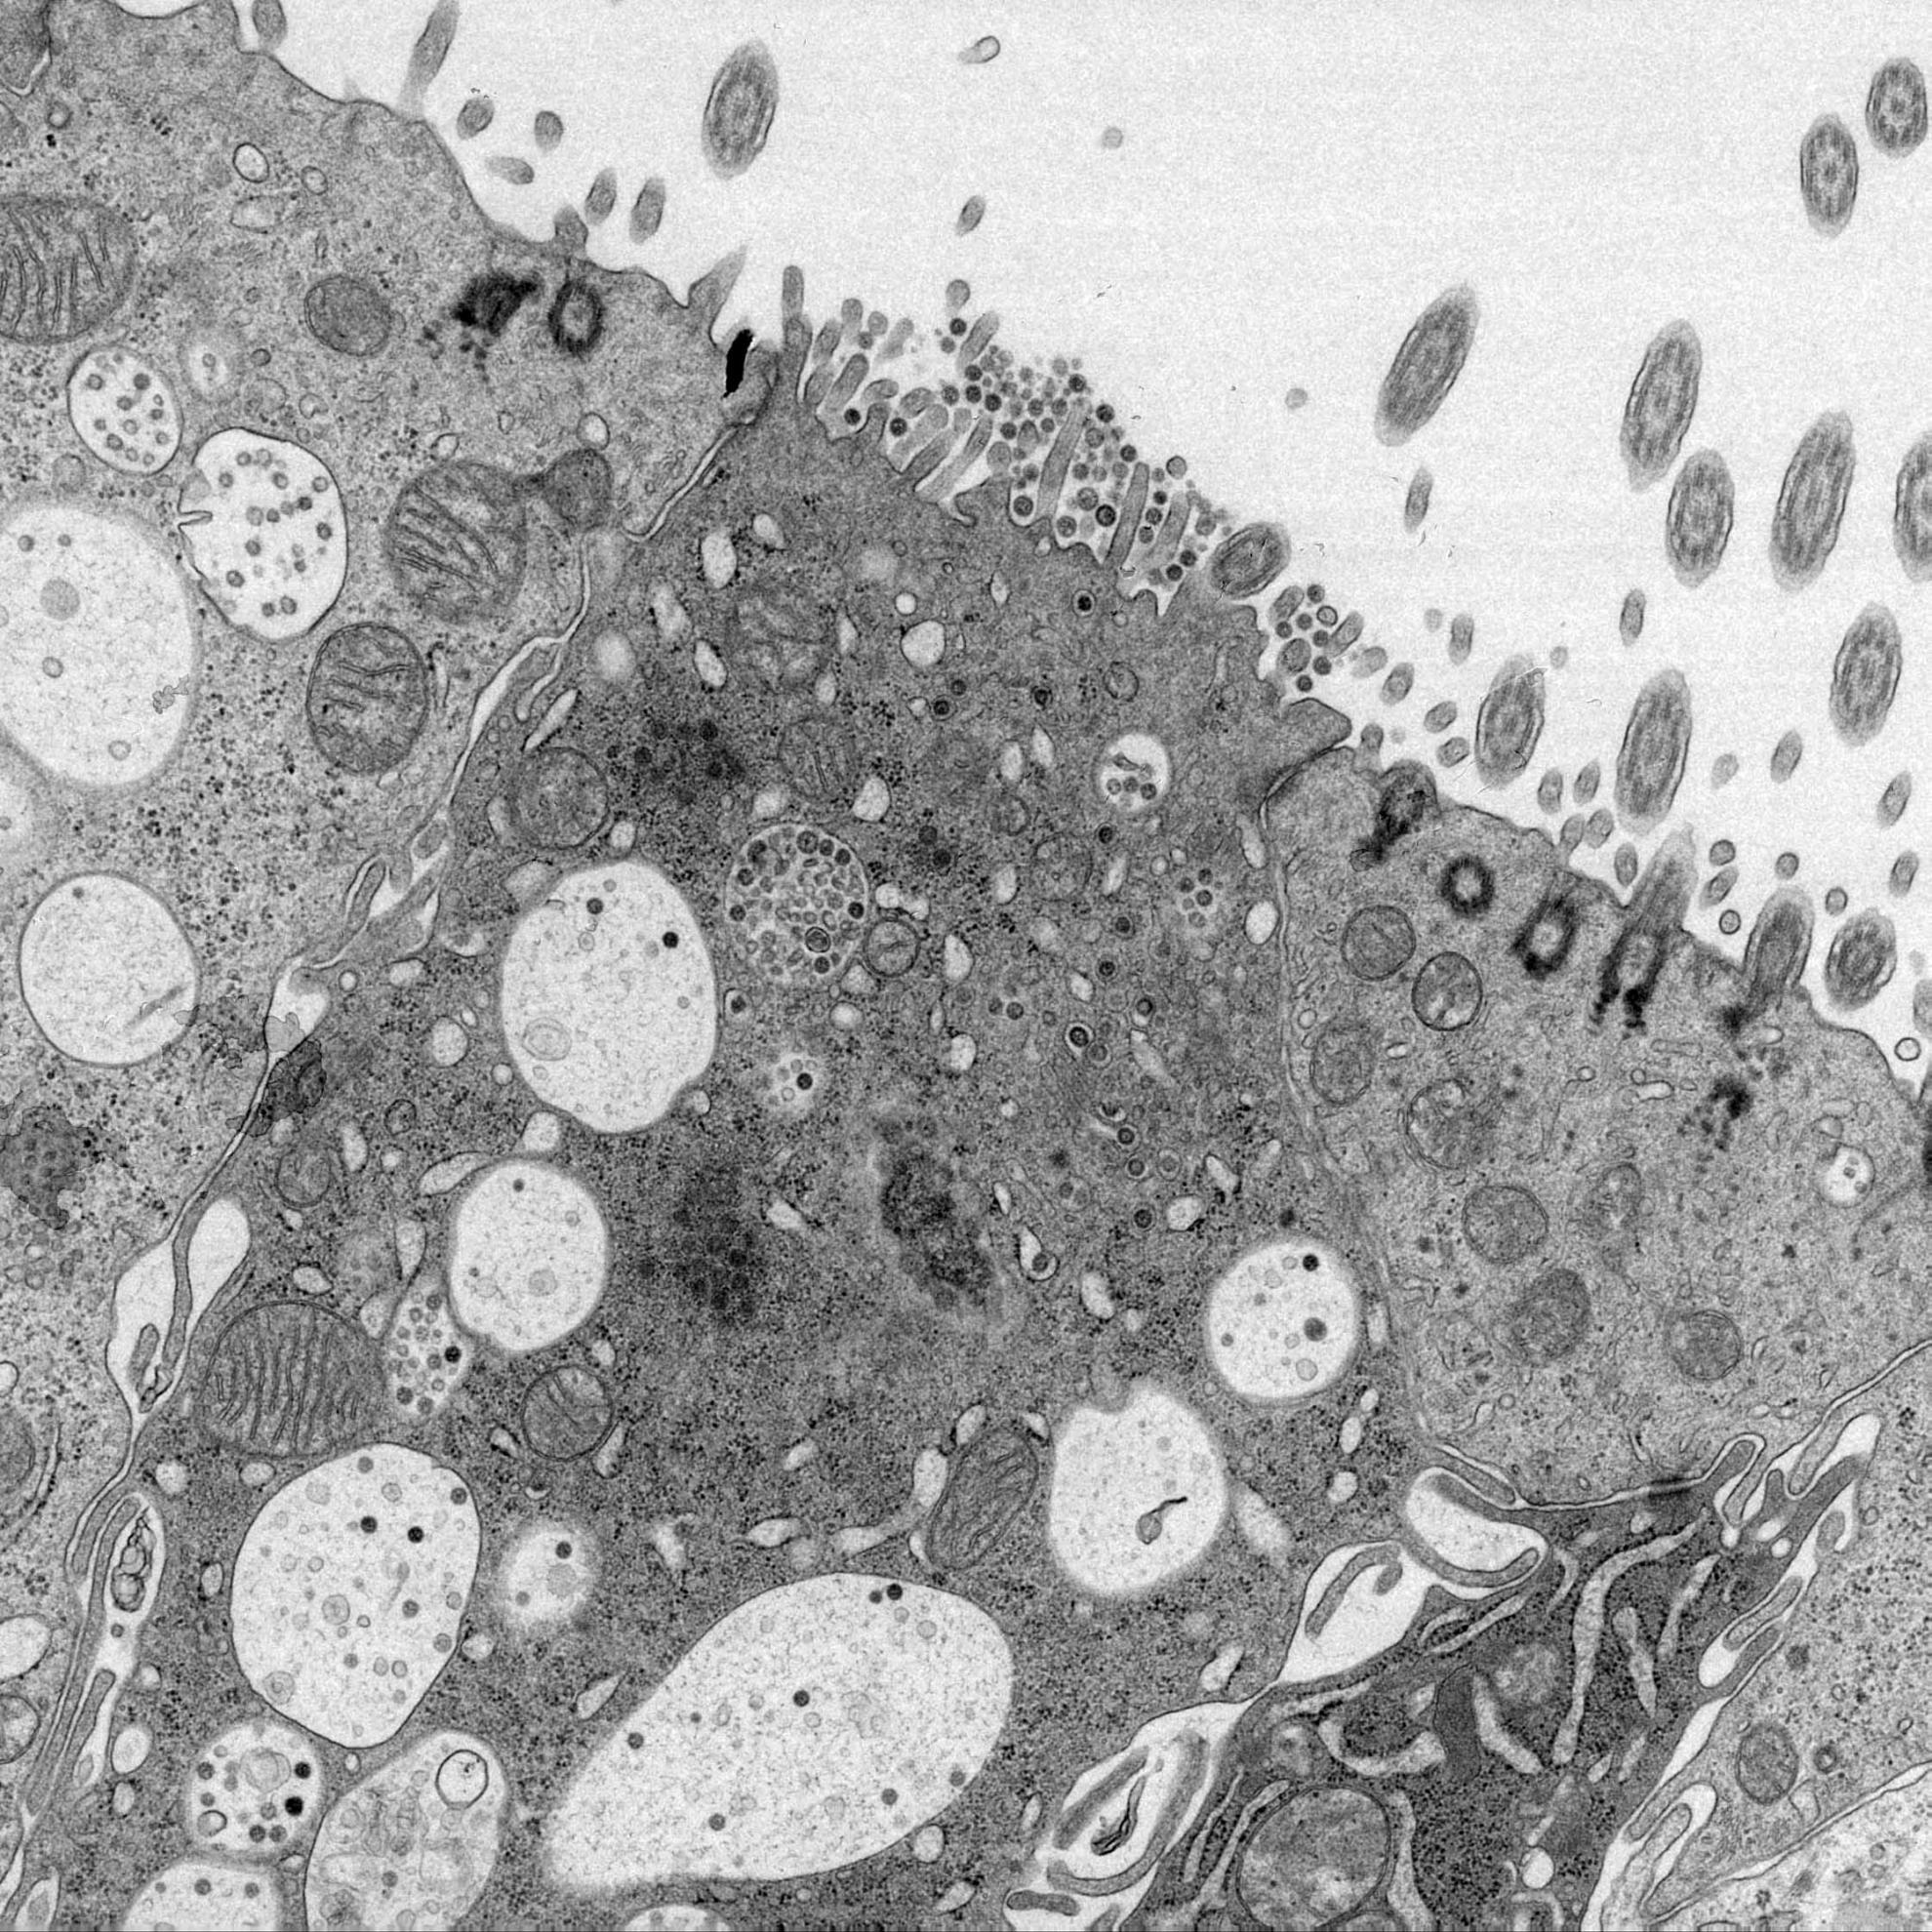

IBV belongs to the Coronaviridae family, genus Gammacoronavirus which has a single stranded RNA genome, surrounded by a nucleocapsid and envelope.